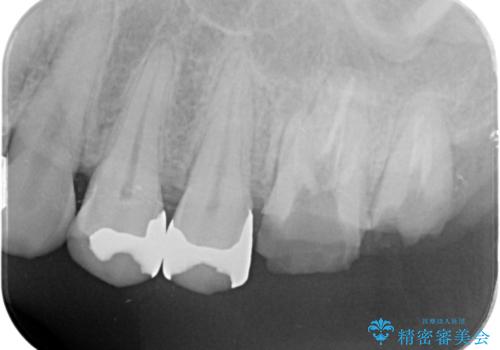

- 銀歯をやりかえたいが他院で抜歯と言われセカンドオピニオンで来院。適合の悪い被せ物が入っており、まずは古い材料、虫歯をとり保存可能か確かめる必要があり、拡大鏡下で全て取り除いたら歯質が歯茎の中まで虫歯がありました。このまま無理やり型取りをして被せ物を作っても不適合な被せ物が入る可能性が高いため歯茎を切り取る手術(ディスタルウェッジ)を行いました。そして再根管治療を行いゴールドの被せ物で治療を行いました。

- PGAクラウン・仮歯 13.2万円×2 精密根管治療(リトリートメント)・コア 16.5万円×2 ディスタルウェッジ 1万円費用は治療当時の料金となります